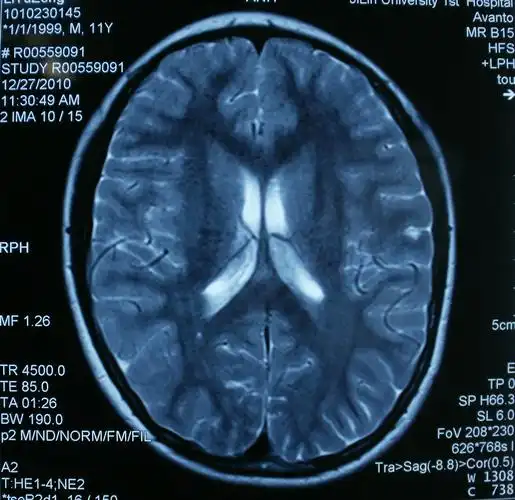

小儿头部mri讨论